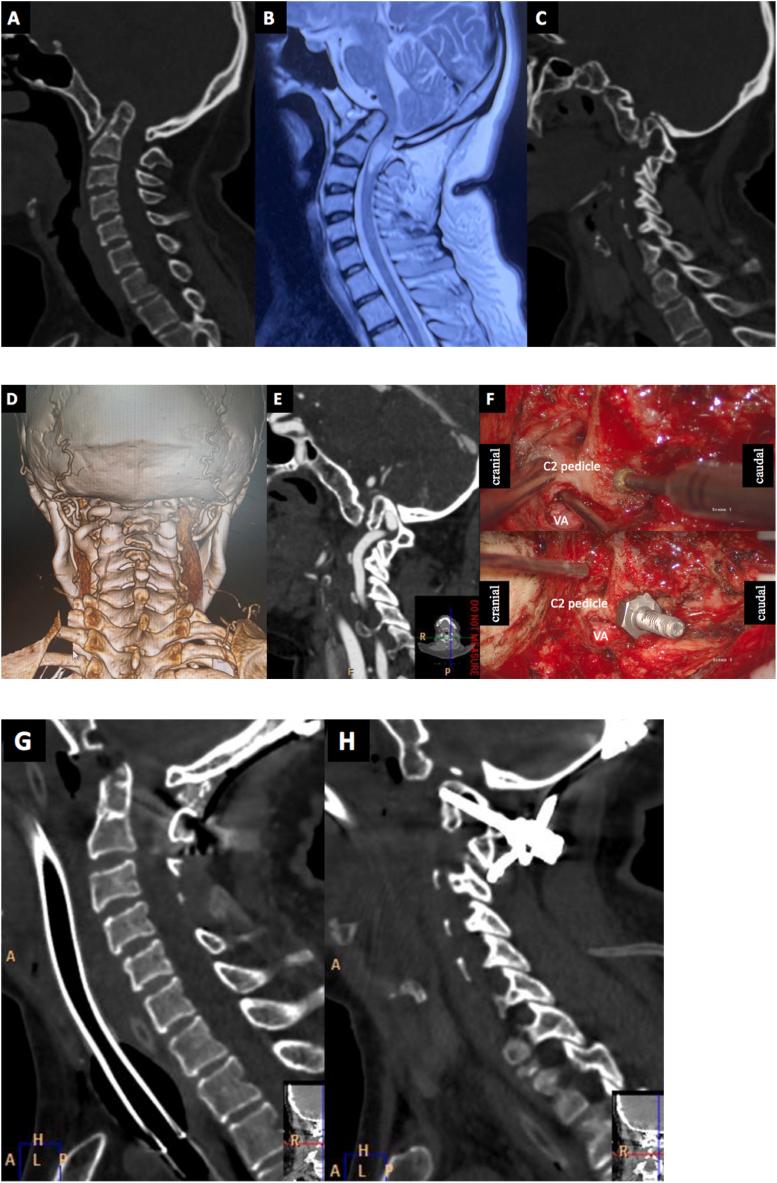

C2 pedicle screw insertion assisted by mobilization of the vertebral artery in cases with high-riding vertebral artery.

OBJECTIVE: To describe the feasibility, safety and efficacy of mobilization of the vertebral artery for C2 pedicle screws in cases with the high-riding vertebral artery (HRVA).

During the period January 2020 to September 2022, fifteen patients underwent posterior occipitocervical fixation in our department. All patients had unilateral HRVA on at least one side that prohibited the insertion of C2 pedicle screws. There were 2 males and 13 females aged 47 ± 11.9 years (range: 17-64 years). After the correction of the vertical dislocation during the operation, the C2 pedicle screw insertion and occipitocervical fixation and fusion were performed using the vertebral artery mobilization technique. A routine three-dimensional reconstructed CT examination was executed to confirm the trajectory of C2 pedicle screws post-operation, and a CT angiography examination was performed when necessary. Neurological function was assessed using the Japanese Orthopedic Association (JOA) scale. The preoperative and postoperative JOA score and the main radiological measurements, including anterior atlantodental interval (ADI), the distance of odontoid tip above Chamberlain line, and clivus-canal angle (CCA), were collected and compared by paired -test.

All 15 patients had atlas assimilation, among which 12 patients had C2-C3 fusion (Klippel-Feil syndrome). Mobilization of the HRVA was successfully completed, and C2 pedicle screws were then fulfilled after the vertebral artery was protected. There was no injury to the vertebral artery during the operation. Meanwhile, no severe surgical complications such as cerebral infarction or aggravated neurological dysfunction occurred during the perioperative period. Satisfactory C2 pedicle screw placement and reduction were reached in all 15 patients. All the patients achieved bone fusion 6 months after surgery. No looseness and shift of internal fixation or reduction loss was observed during the follow-up period. Compared to the preoperative, the postoperative JOA score and the main radiological measurements were remarkably improved and statistically significant.

C2 pedicle screw insertion assisted by mobilization of the vertebral artery is safe and considerably effective, providing a choice for internal fixation in cases with high-riding vertebral arteries.